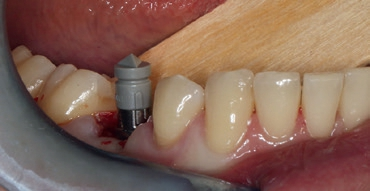

Obwohl ursprünglich als Sofortimplantation geplant, erfolgten die schonende Extraktion (Abb. 3) und die Implantation im Abstand von einer Woche. Das Ziel war es, die apikale Ostitis mit kurz vor dem OP-Termin beginnender bukkaler Schwellung abheilen zu lassen und eine ausreichende Entzündungsfreiheit zu erreichen (Abb. 7). Beim Einsetzen des Implantats kam die Bohrschablone zum Einsatz. Um die Lagestabilität der Schablone zu gewährleisten, war es wichtig, diese ausreichend groß zu dimensionieren (Auflage Zahn 33 bis 46); Sichtfenster ermöglichen es dabei, die planmäßige und vollständige Auflage der Schablone auf dem Zahnbogen jederzeit zu kontrollieren.

Nach der geführten Implantatbettaufbereitung wurde das Astra Tech Implant System EV 4,8C × 13 mm durch die Hülse hindurch mit Höhenanschlag in seine geplante Position inseriert (Eindrehmoment final: 45 Ncm) (Abb. 8 bis 10). Die Lage des Implantats wurde mit einer intraoralen Röntgenaufnahme postoperativ überprüft (Abb. 11). Es folgte die digitale Abformung mit der CEREC Omnicam: Um die Implantatposition exakt zu übertragen, wurde ein Scanbody platziert (Abb. 12). Der dabei erzeugte Scan wurde für das präzise Design eines Provisoriums mit der Abformung des Milchzahnes überlagert und im Anschluss gefräst (Abb. 13). Das Kunststoffprovisorium wurde mit der dazugehörigen TiBase verklebt (Multilink Hybrid Abutment, Ivoclar Vivadent). Zuvor wurden sowohl die TiBase als auch das Zirkonabutment sandgestrahlt, im Ultraschallbad gereinigt und im Anschluss silanisiert (Monobond plus, Ivoclar Vivadent). Im nächsten Schritt wurde das Provisorium mit dem Implantat okklusal verschraubt (Abb. 14) und mit Komposit verschlossen (Abb. 15 bis 17). Um eine Überbelastung des Implantats während der Einheilzeit zu vermeiden, war eine Nonokklusion von 0,5 bis 1 mm zum Antagonisten zu beachten. Dazu gehörte auch die Empfehlung an die Patientin, das Provisorium in den ersten Monaten nur eingeschränkt zu belasten (weiche Kost).